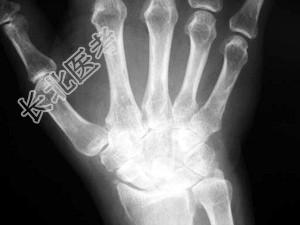

- 单项选择题女,50岁, 手指关节肿痛,晨僵, 结合图像,最可能诊断是 ( )

A、关节结核

B、牛皮癣性关节炎

C、痛风性关节炎

D、类风湿关节炎

E、Reiter综合征